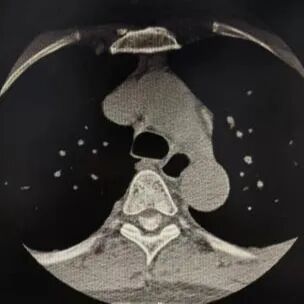

CT可以发现椎管占位病变,肿物钙化